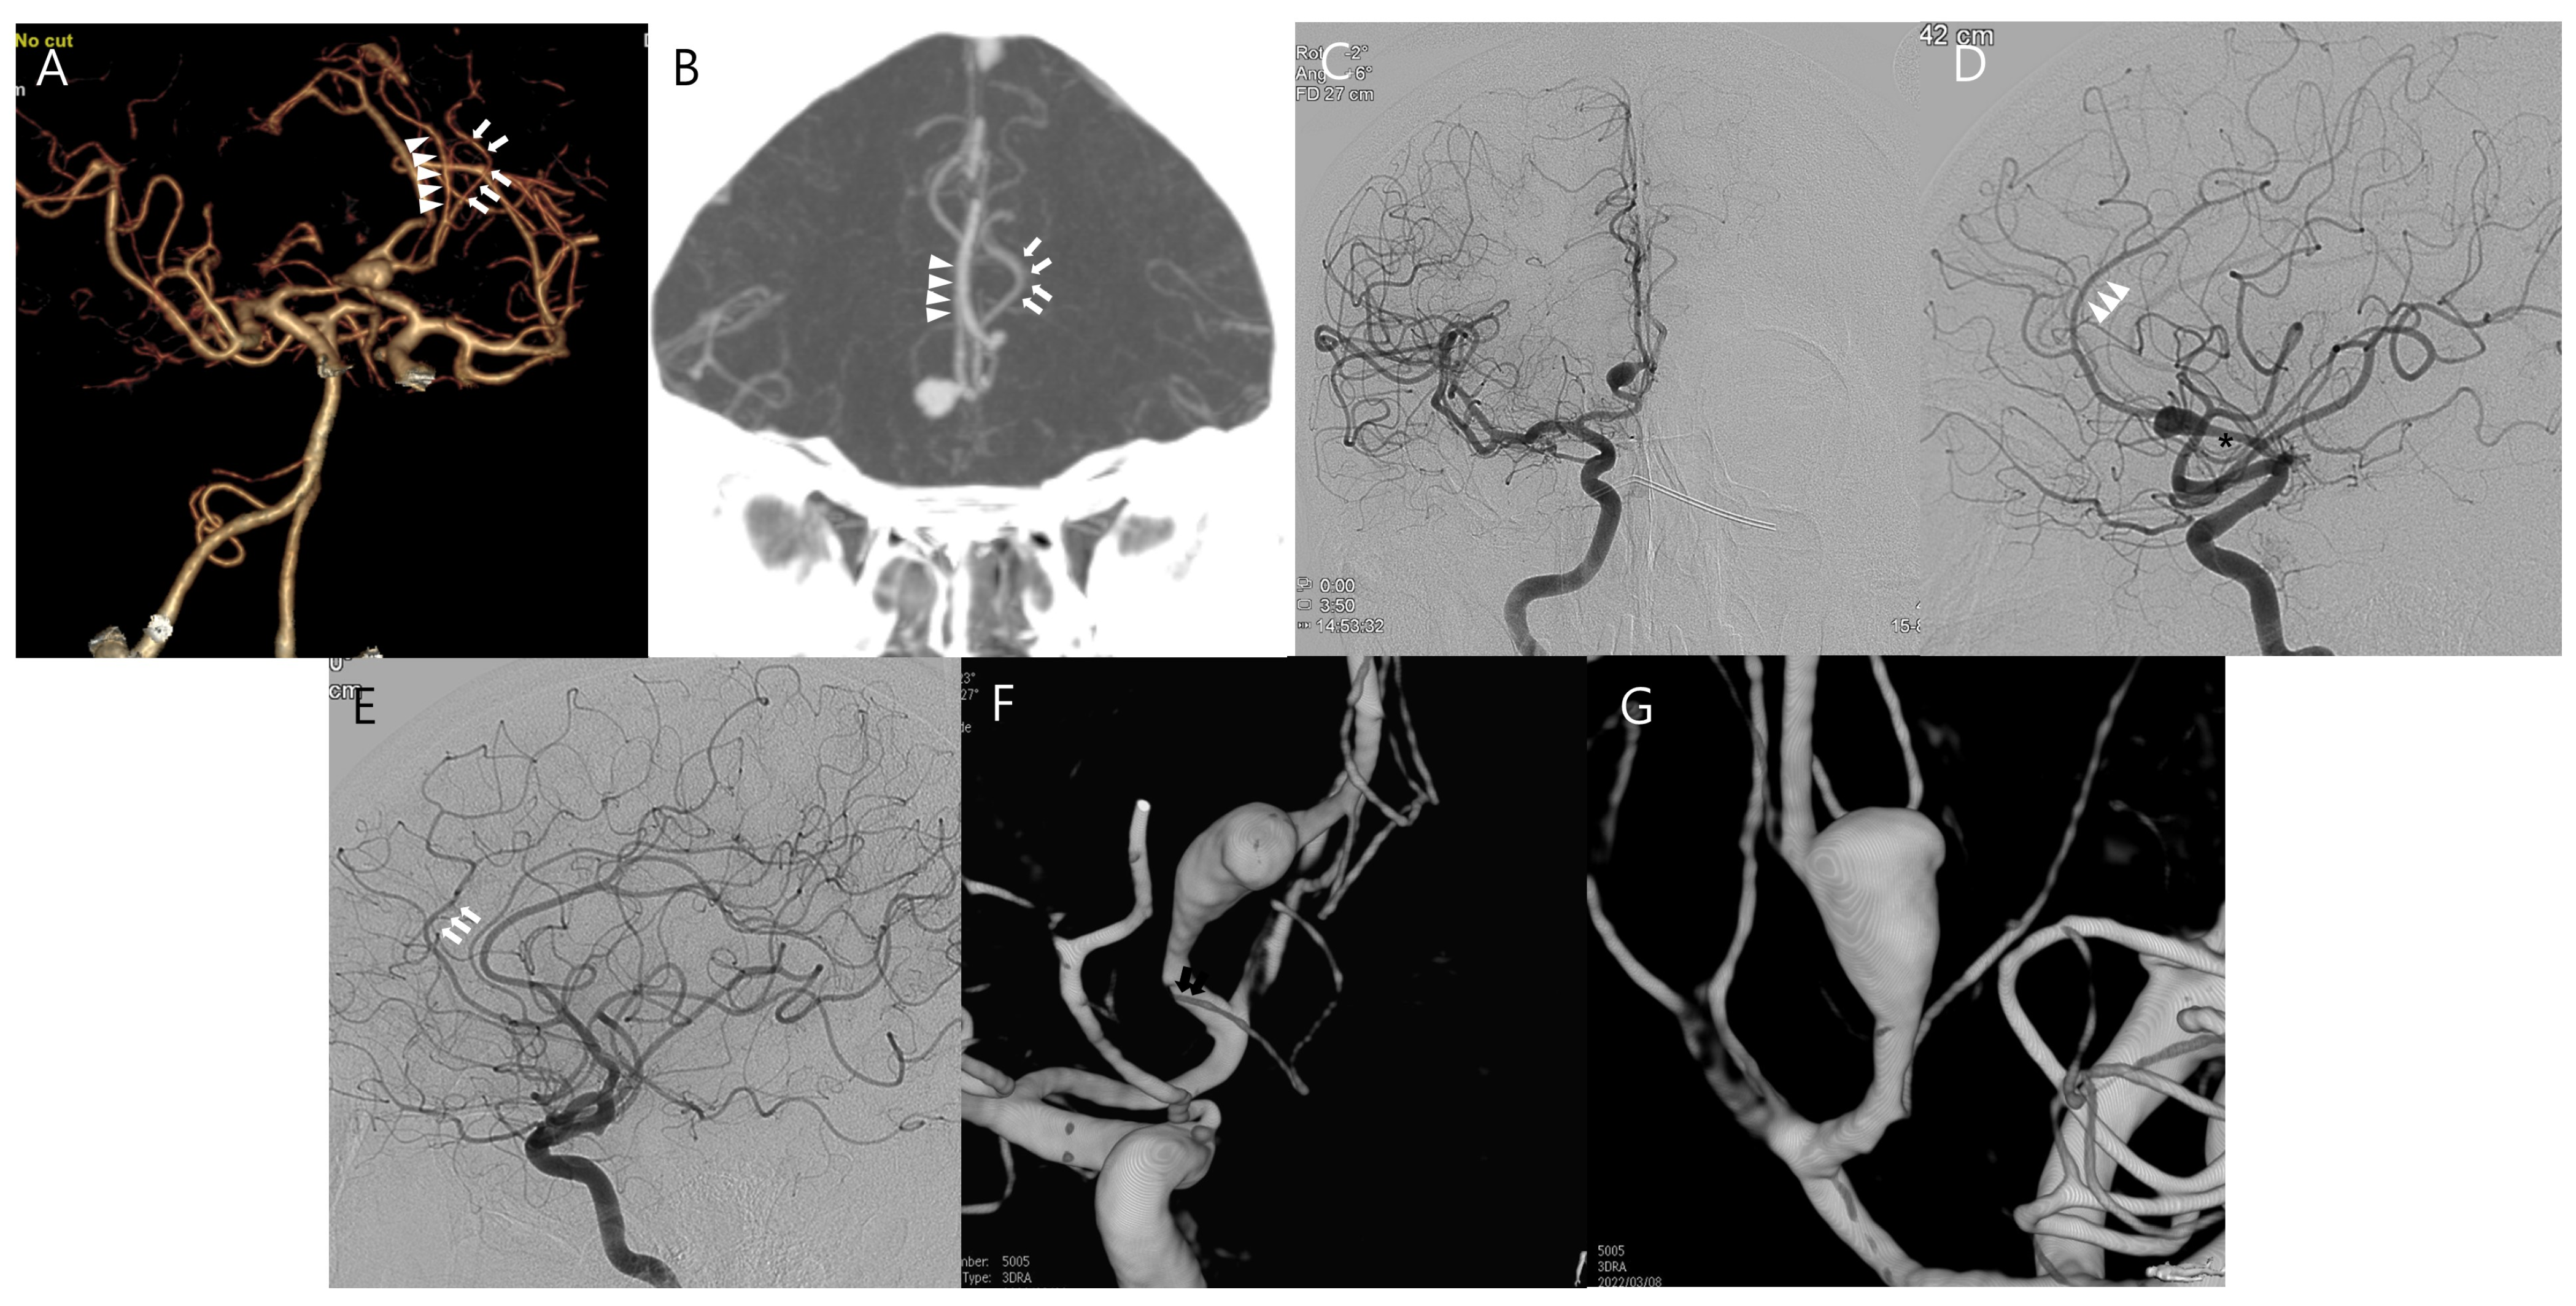

Combined Treatment of Large Fusiform A2 Aneurysm with End-to-Side Extended Superficial Temporal Artery–A3 Bypass Using Contralateral Superficial Temporal Artery Interposition Graft and Endovascular Aneurysm Trapping: A Case Report and Literature Review

2. Case Presentation

Kim, Y.-S.; Kim, J.-W.; Kim, W.-B.; Baek, B.-H.; Yoon, W.; Kim, T.-S.; Joo, S.-P. Combined Treatment of Large Fusiform A2 Aneurysm with End-to-Side Extended Superficial Temporal Artery–A3 Bypass Using Contralateral Superficial Temporal Artery Interposition Graft and Endovascular Aneurysm Trapping: A Case Report and Literature Review. J. Clin. Med. 2025, 14, 2927. https://doi.org/10.3390/jcm14092927